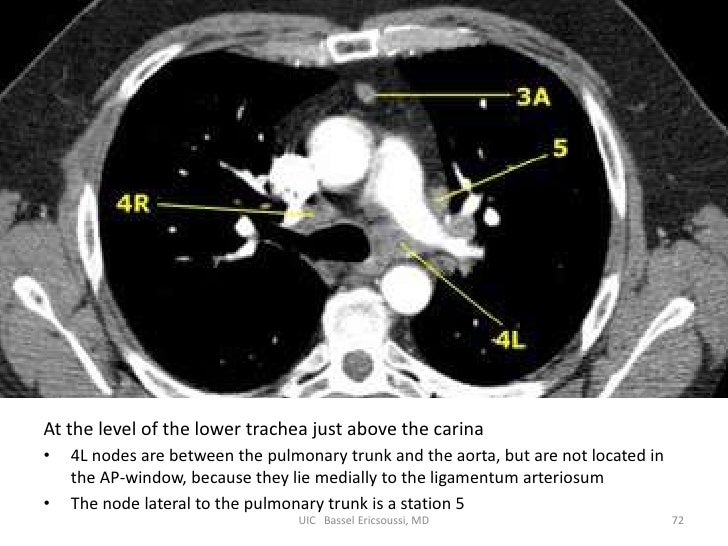

Внутригрудные лимфоузлы на кт

Внутригрудные лимфоузлы на кт 110 фото